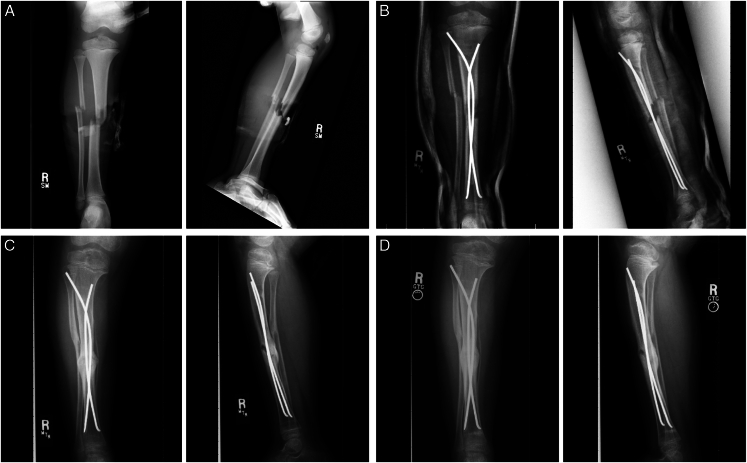

Abstract Image